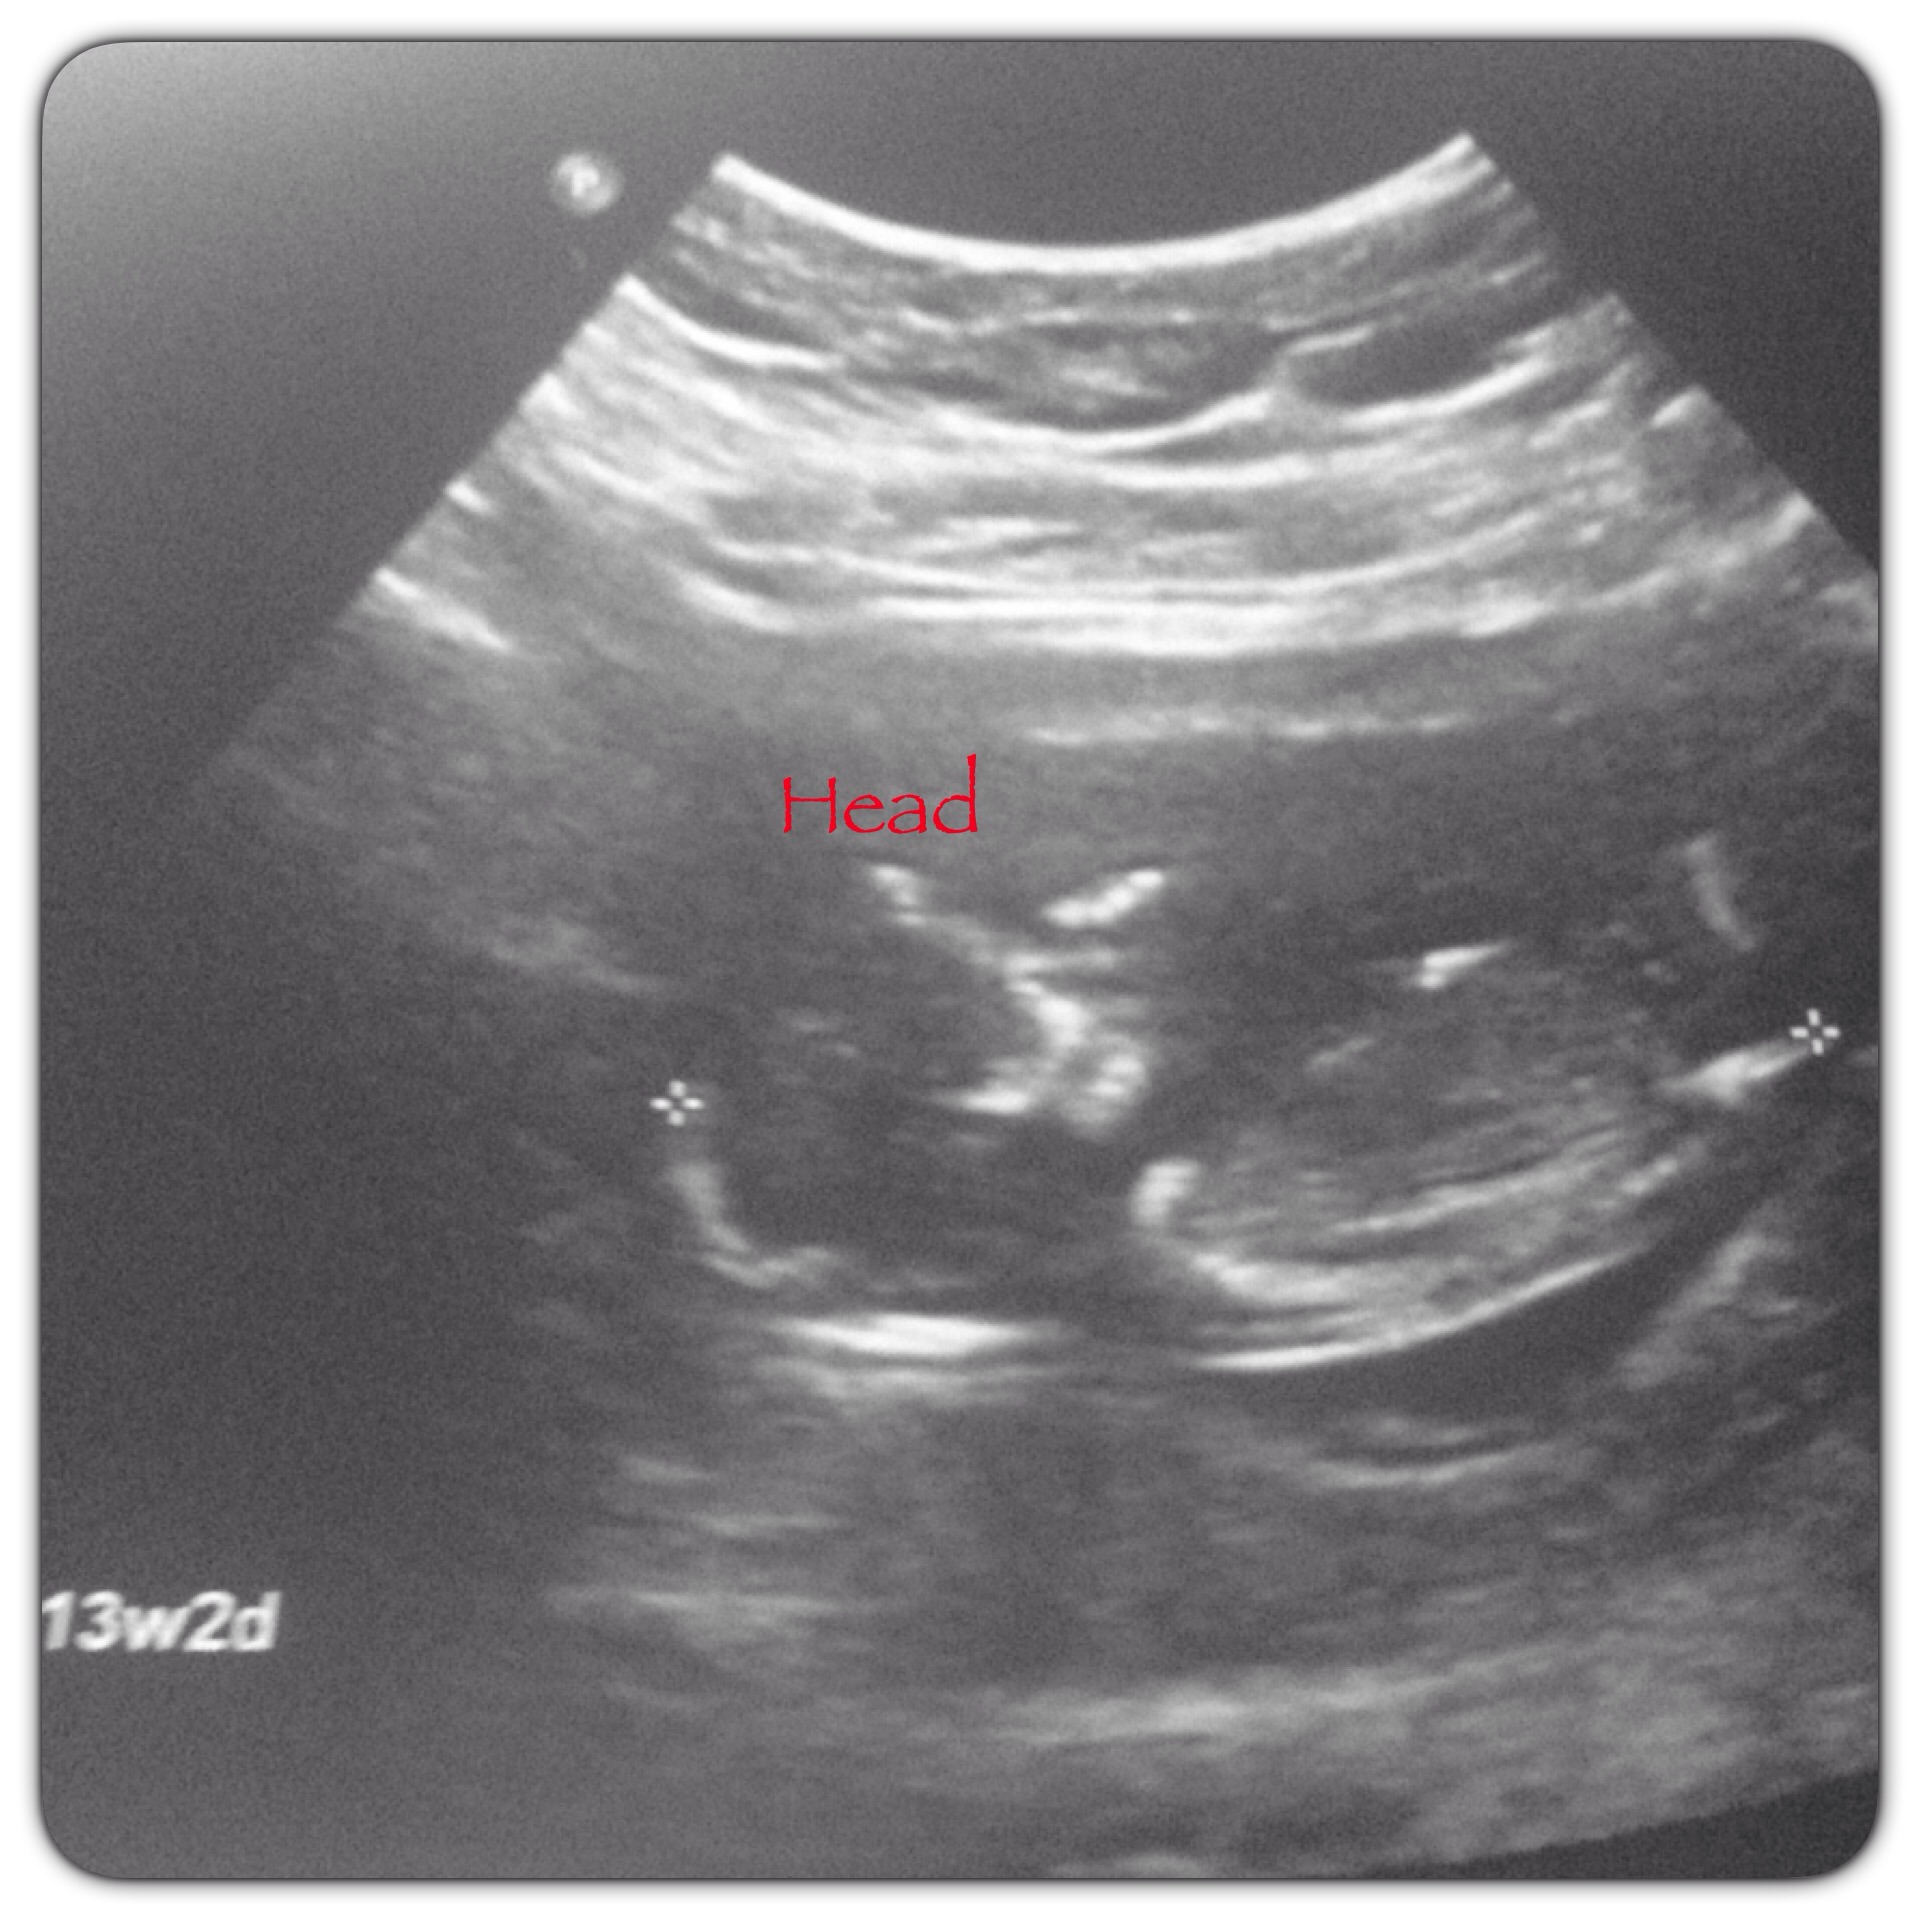

That head though... I'm saying a girl right now...

Any guesses at the sex for fun. Obviously, it's WAY too early.